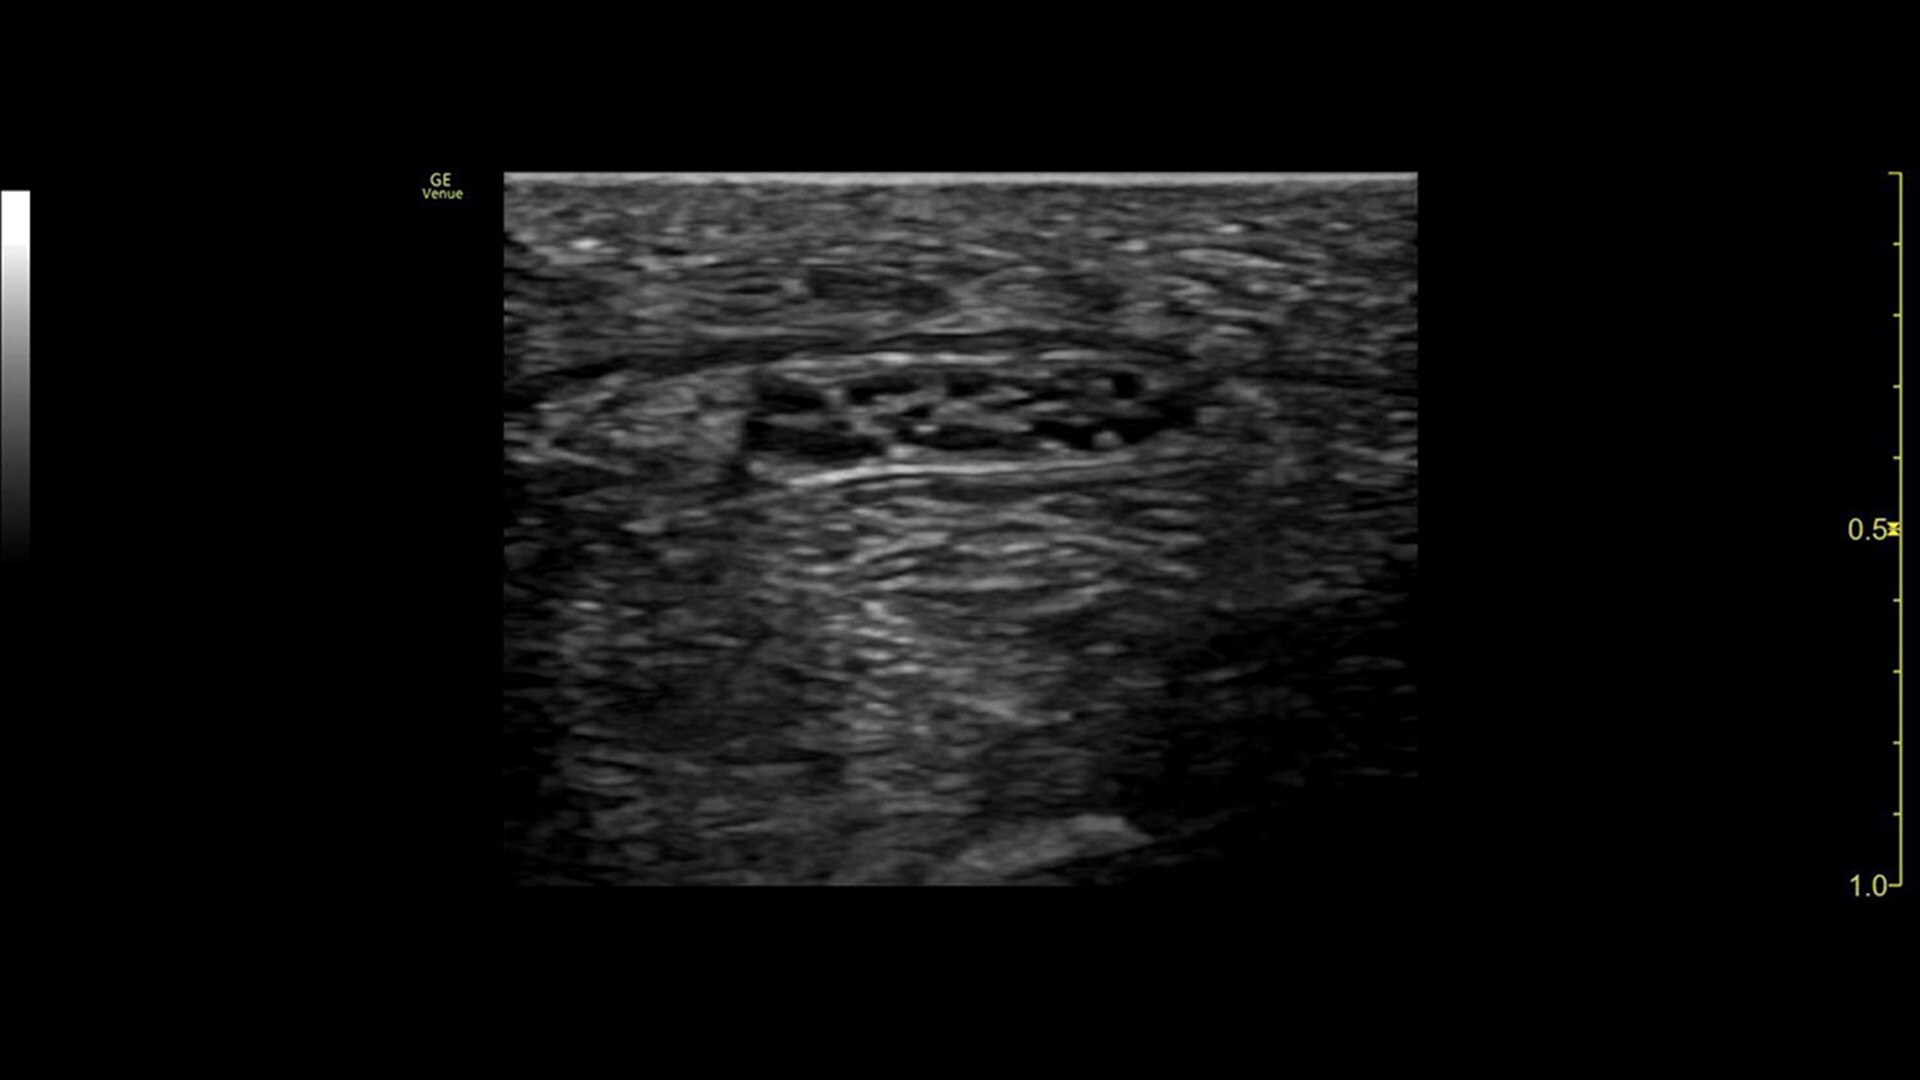

Offering anesthesiologists an effortless, multi-purpose ultrasound system, the Venue™ family helps confidently decrease the risk of complications during nerve block procedures. Vibrant images and a powerful suite of tools allow you to see nerves and surrounding anatomy quickly and clearly to optimize local anesthetic distribution.

Vibrant visuals

Clear needle visualization enables effective procedures

Accurate imaging for enhanced clinical confidence

Helping improve patient outcomes by reducing error rates, Venue’s imaging software is optimized to help the nerve stand out from other types of tissue. Allowing you to differentiate between the needle and patient anatomy with confidence, Venue family systems guide you with a real-time view of anatomy, needle advancement and local anesthetic spread.